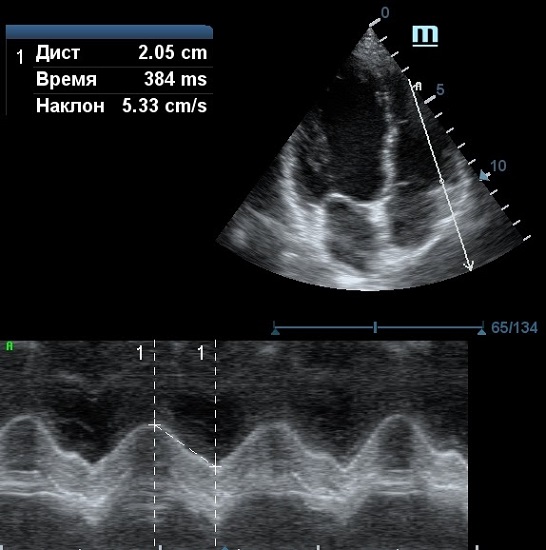

MAPSE - амплитуда движения латерального кольца митрального клапана, позволяет рассчитать фракцию выброса по формуле EF = 4.8 × MAPSE (mm) + 5.8, очень быстрый и гораздо более точный («прародитель Strain») метод чем широко распространенный метод Teicholtz. В современных приборах можно легко добавить свою формулу при отсутствии ее в стандартном калькуляторе. Главным условием является проведение линии М-режима параллельно стенке левого желудочка в апикальном четырехкамерном сечении, что легко достигается при использовании функции Free Xros.